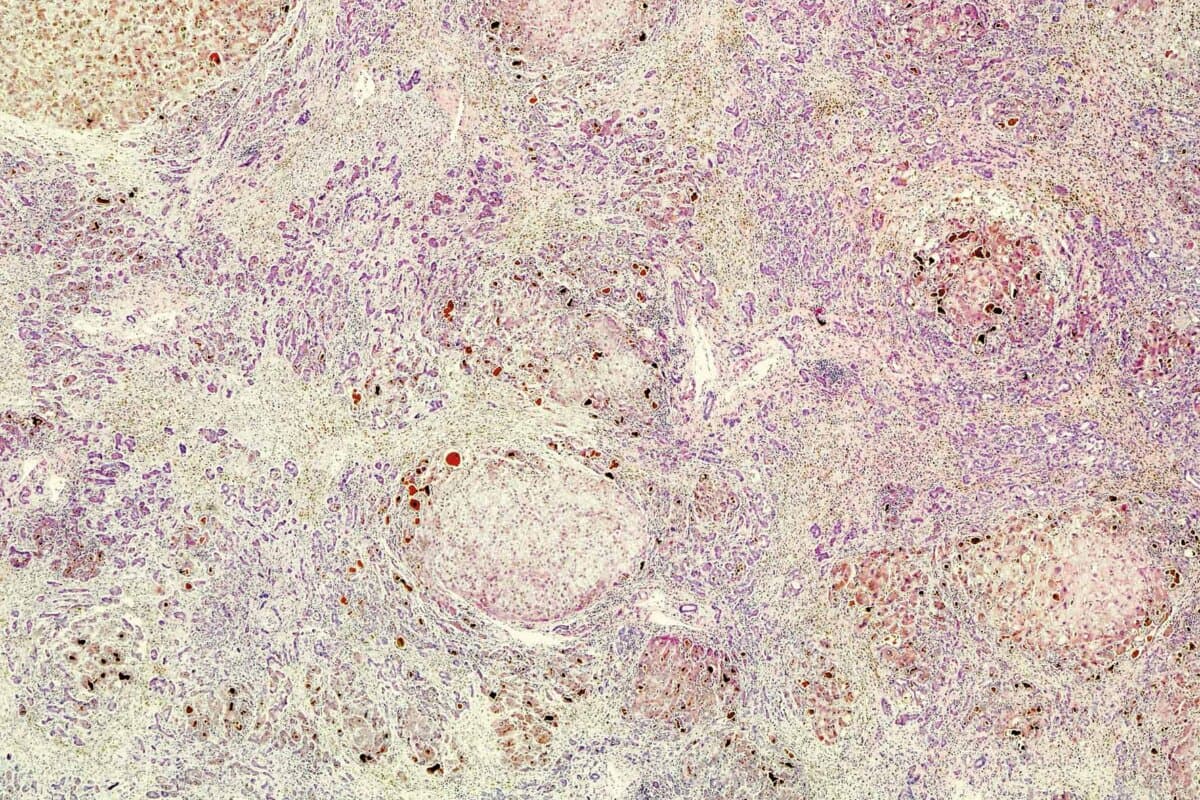

Bei der primären biliären Cholangitis (PBC) entzünden sich die kleinen intrahepatischen Gallengänge chronisch und sterben schliesslich ab, schreibt David Assis von der Yale School of Medicine, New Haven (1).